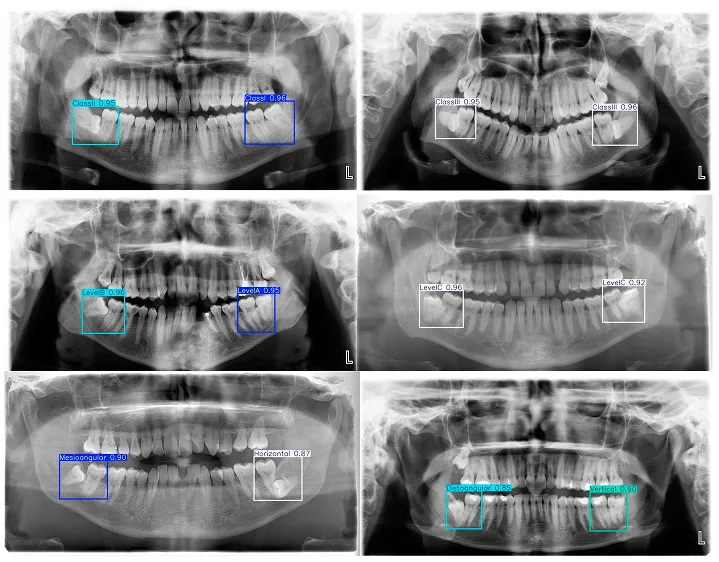

La famigliaYOLO Ultralytics include Ultralytics YOLOv5, Ultralytics YOLOv8, Ultralytics YOLO11e l'ultima versione, Ultralytics . Questi modelli non detect anomalie detect immediatamente.

Per identificare tumori, lesioni, fratture o altre anomalie, possono essere ottimizzati o addestrati in modo personalizzato su set di dati di immagini mediche etichettati che insegnano loro quali oggetti o anomalie cercare all'interno delle immagini mediche.

Fig. 1. Utilizzo YOLO analizzare i raggi X (Fonte)

Una volta ottimizzati, modelli come YOLO26 possono fungere da assistenti visivi nei flussi di lavoro diagnostici. In particolare, la loro velocità li rende utili in ambienti clinici molto trafficati, dove è necessario esaminare rapidamente grandi volumi di dati di imaging.